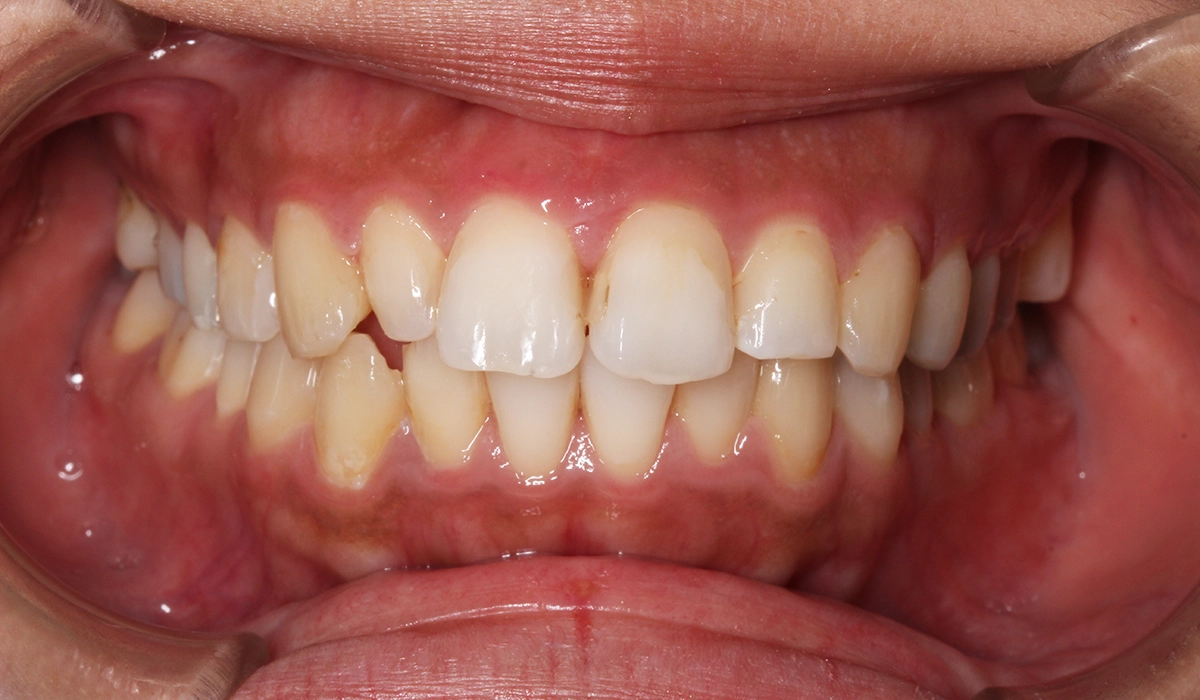

今回ご紹介する患者様は、上下の歯並びのガタツキを気にされており、矯正検査後叢生Ⅱ級と診断いたしました。

術前:正面

術後:正面